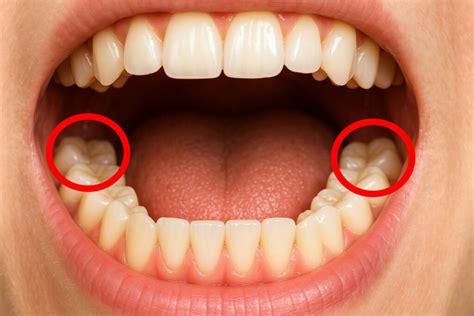

Es importante conocer las distintas condiciones en que pueden darse las muelas del juicio, así como el procedimiento de extracción.

En general, es importante ser consciente de que cuando salen las muelas del juicio, pueden causar distintos problemas, como dolor o infección, y que a veces puede ser necesario extraerlas.